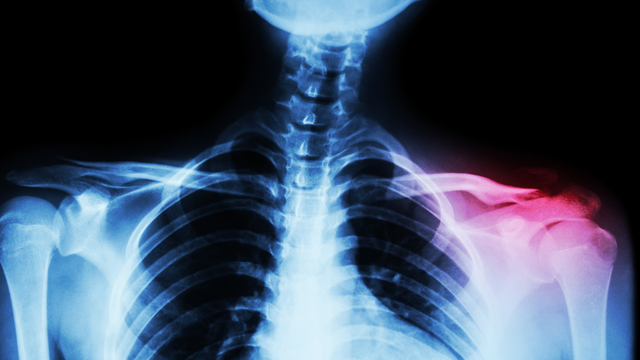

Gãy xương đòn